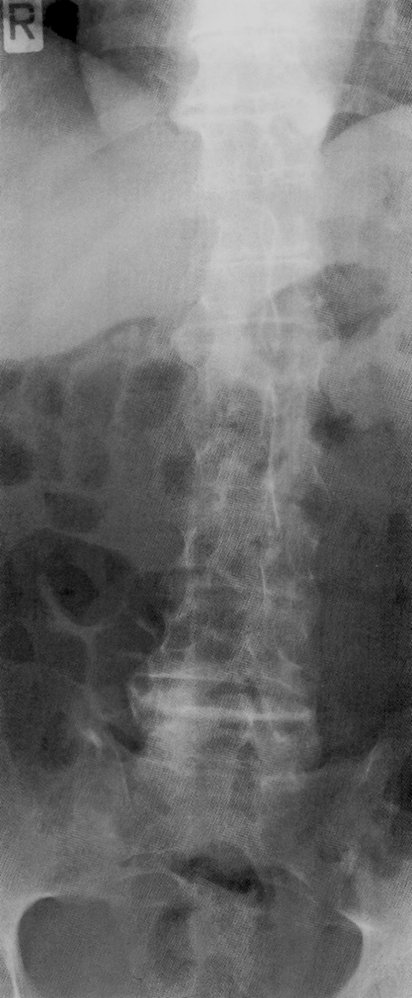

X-ray

Sacroiliac joints (PA view) [4]

• Indication: best initial test to confirm the diagnosis of AS and evaluate disease severity

• Characteristic findings (usually symmetrical)

• Signs of sacroiliitis: erosion and sclerosis (increased radiodensity) of the sacroiliac joints

• Ankylosis: fusion of the articular surfaces

Spine (AP and lateral views)

• Dagger sign

• A radiodense line running through the center of vertebral bodies on AP view

• Caused by ossification of vertebral ligaments